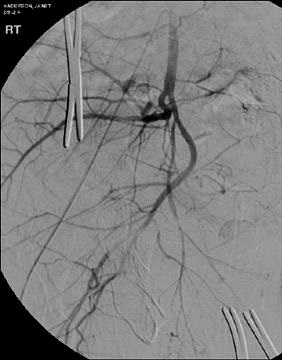

病例:交通事故,96F,被挤在Car vs Wall之间。Hct 20.5,BP 106/? 心率94,2单位 红血球后,血压130,心率106.

同一病人

交通事故,96F,Car vs Wall